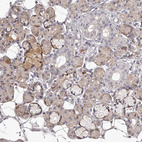

Immunohistochemical staining of human breast shows moderate to strong cytoplasmic and membranous positivity in glandular cells.